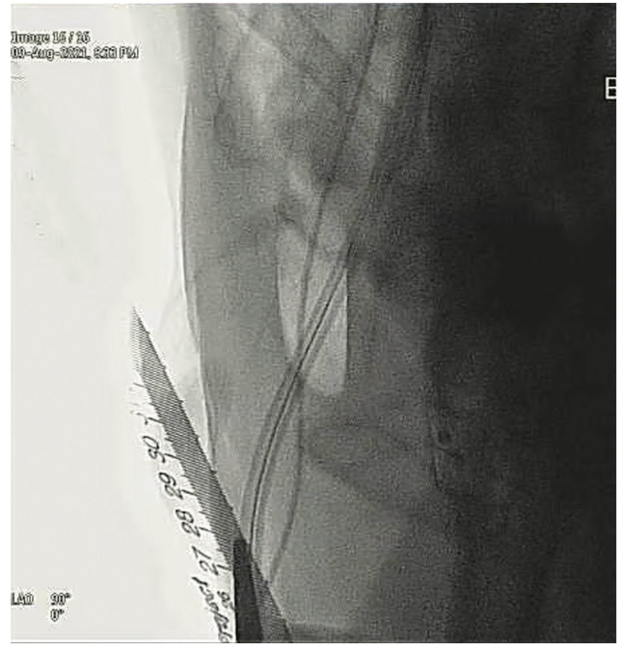

3. A ruler with a sterile cover was placed parallel to the Impella driveline in the coronal plane under fluoroscopy (Figures 1-2).

4. Without changing the alignment of the ruler, an angiogram at a left anterior oblique 90-degree (true lateral) angle was performed, with contrast injected via a cross-over internal mammary (IM) catheter. Apart from measuring the skin-arteriotomy distance, this angiogram also confirmed the position of the arteriotomy, which was well above the femoral bifurcation.

5. Calibration of the length was done, and the distance between the skin (marked with the metal pointer) to the Impella arteriotomy was measured (Figure 3).